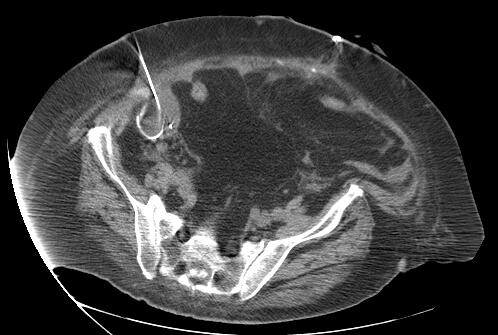

23 year old female with fever and RLQ tenderness s/p appendectomy.

Comment: This case demonstrates performance of a straight-forward CT-guided drainage. Once the abscess was localized on CT and the access site confirmed with a 25g needle, the collection was accessed with a Chiba needle and a guidewire was coiled within the collection. Serial dilatation was then performed so that a pigtail drainage catheter could be placed within the collection for drainage.